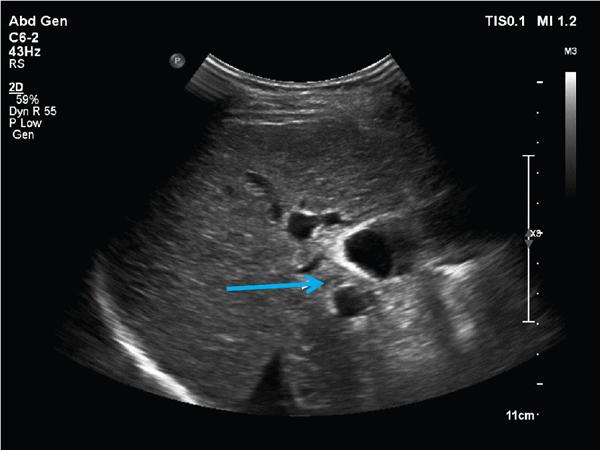

Shrinivas B. Desai, Ritu K. Kashikar, Aman Snehil, Ajay Jhaveri Cirrhosis is a late stage of irreversible scarring of the liver causing abnormality in liver structure and function. Multiple conditions and factors can cause repeated liver damage and scarring ultimately leading to cirrhosis. The most feared complication of liver cirrhosis is the development of hepatocellular carcinoma (HCC). Portal hypertension (PHT) is seen with a variety of conditions but cirrhosis happens to the most important cause. Imaging plays a vital role in noninvasive diagnosis and treatment planning of both cirrhosis and PHT. Liver imaging reporting and data system (LI-RADS) is a standardized reporting system assigning an observation risk of representing HCC. This chapter focuses on discussing aetiologies and imaging of PHT with a lucid review of L1-RADS 2018 version. The portal blood circulation is a unique circulatory circuit as it connects two capillary beds between the liver parenchyma at one end and the gastrointestinal tract and splenic parenchyma at the other end. The portal system ramifies in the liver and ultimately ends in the hepatic sinusoids from where the blood ultimately drains into the inferior vena cava (IVC). The portal vein (PV) originates from the capillary beds in the stomach, intestine and the spleen. The main PV is formed behind the neck of the pancreas by the confluence of the superior mesenteric vein (SMV) and splenic vein. It continues to the porta hepatis where it bifurcates into the left and right branches as it carries nutrient rich but oxygen poor blood to the liver (Fig. 9.9.1). The PV makes up for 75%–80% of the liver’s blood supply while the hepatic artery which arises from the celiac trunk makes up for the remaining 25%. A pathological increase in the portal venous pressure is referred to as PHT. PHT is most often a sequel of chronic parenchymal liver disease and leads to major life-threatening complications due to bleeding from the collateral circulation (most commonly oesophageal varices). Direct measurement of portal pressure (PP) is invasive and often not feasible in most patients and thus imaging plays an important role in the diagnosis of PHT and its complications. The normal portal venous pressure ranges between 5 and 10 mmHg, which is the equivalent of 7–14 cm H2O. The normal hepatic venous pressure gradient (HVPG) is the pressure gradient between the PV and the IVC, is typically 1–5 mmHg. Presence of PHT is indicated by a wedged hepatic venous pressure of more than 5 mmHg. Other definitions include a splenic pressure of more than 15 mmHg or an intraoperative PP of greater than 30 cm H2O. The complications of PHT are seen when HVPG is greater than 10 mmHg and hence this value defines clinically significant PHT. Variceal bleeding is seen with a pressure greater than 12 mmHg. In ideal conditions, the portal circuit is a high flow, low resistance circuit as it has to allow substantial flow rates of 700–1000 mL/min to the hepatic parenchyma from the gastrointestinal tract. Anatomical changes in the organization of the hepatic lobule can result in rise in the portal resistance. These can occur in the form of collagen deposition in the space of Disse, fibrotic scars formed due to regenerative nodule (RN) formation, loss of normal elasticity of the endothelium and distal venous thrombosis. Changes in splanchnic haemodynamics due to factors that increase splanchnic blood flow and increase in intrahepatic vascular resistance due to transformation of stellate cells into myofibroblasts also contribute to the increase in PP gradient. In Western countries, alcoholic cirrhosis and viral cirrhosis are the leading causes of PHT and oesophageal varices. The viral causes form majority of cases leading to cirrhosis and PHT in the Far East and Middle Eastern countries while Schistosomiasis remains an important cause in the African countries. Worldwide, nonalcoholic steatohepatitis (NASH) and hepatitis C are the emerging causes of chronic liver disease (CLD) and PHT. PHT can be classified as cirrhotic and noncirrhotic depending on whether it is associated with cirrhosis or not. This distinction is important as noncirrhotic causes like PV thrombosis are at high risk of development of bleeding but tend to have a better chance of surviving a variceal bleed than a patient with decompensated alcoholic cirrhosis due to preserved hepatic synthetic functions in the former. PHT can also be classified on the basis of the location of the pathology into prehepatic, hepatic and posthepatic causes. Hepatic causes can further be divided into presinusoidal, sinusoidal and postsinusoidal. The causes of portal hypertension have been denoted in Table 9.9.1. The direct measurement of the PP by measuring the HVPG is invasive, expensive not readily available in all patients. Thus, imaging plays an important role in the diagnosis of PHT. Various modalities are used for the imaging diagnosis of PHT. Ultrasonography (USG) and Doppler evaluation have the advantage of being inexpensive, readily available and bedside modality (Table 9.9.2). The role of ultrasound and Doppler in imaging of PHT is to: Grey scale imaging is useful in evaluating the splenoportal anatomy. The evaluation should begin with the liver morphology. Signs of cirrhosis like nodularity of the liver surface with relative atrophy of the right lobe and prominence of the left lobe and caudate should be looked for. Hepatic echotexture appears coarse and more echogenic (Table 9.9.3). Increase in portal venous diameter is a sign of PHT (Fig. 9.9.2). Portal venous diameter of more than 13 or 15 mm has low sensitivity for diagnosing PHT of only 40%–12.5%, respectively. Absolute measurement of the portal diameter as a sign of PHT is also fallacious as in presence of collateral circulation or hepatofugal flow; there may actually be a decrease in the PV diameter. Therefore, a more accurate sign is respiratory variation of PV diameter. An increase in PV diameter of less than 20% with deep inspiration has been reported to indicate PHT with a sensitivity of 80% and specificity of 100%. This has been reported to be an accurate indicator of cirrhosis. Hepatic vein straightness, uniformity of vein wall echogenicity and visualization of at least 1 cm segment of the hepatic vein are the parameters used for evaluation. Splenomegaly is defined as bipolar splenic diameter of greater than 12 cm or largest splenic cross-sectional area passing through the hilum of greater than 45 cm2, and occurs secondary to PHT (Fig. 9.9.3). A total of 65%–80% patients with cirrhosis have splenomegaly on ultrasound. Patients with cirrhosis due to viral hepatitis and primary biliary cirrhosis show splenomegaly more frequently than those with alcoholic cirrhosis. This is an accurate sign of PHT. USG is extremely sensitive with respect to detecting subclinical ascites. Perihepatic space is the most usual site of visualization of minimal ascites. In normal subjects, this ratio is approximately 0.07 and a value above 0.1 suggests the diagnosis of PHT with a 95% sensitivity and specificity. The normal spectral waveform of the hepatic artery is a low resistance flow pattern with forward flow in diastole and a resistivity index in the range of 0.5–0.7. In PHT, the resistivity index of the hepatic artery increases with high resistance flow pattern due to increased peripheral vascular resistance. Resistance index (RI) > 0.78 in the intrahepatic branches of the hepatic artery has been reported to have a sensitivity of 50% and a specificity of 100% for the detection of PHT (Fig. 9.9.11). Pulsatility index (PI) > 1.05 suggests severe PHT with a sensitivity of 86% and specificity of 88% (Fig. 9.9.11). Patency of hepatic veins should be evaluated to rule out Budd–Chiari syndrome as a cause of PHT. The normal hepatic venous waveform (HVW) reflects right atrial activity and this results in a triphasic waveform with one positive and two negative waves. In PHT, this waveform becomes monophasic or biphasic. A monophasic HVW has a sensitivity and specificity of 74% and 95%, respectively, in the diagnosis of severe PHT (Fig. 9.9.12). Dilatation of the splanchnic veins – the SMV and the splenic vein – more than 11 mm are suggestive of PHT with a sensitivity and specificity of 72% and 100%, respectively. A reduction in the respiratory variation of the splenic vein and SMV to less than 40% had a sensitivity and specificity of 79.7% and 100%, respectively, for the diagnosis of PHT (Fig. 9.9.13). The splenic artery reveals an increase in the resistivity index and an RI of >0.63 and a PI of >1 have a sensitivity and specificity of 84.6% and 70.4% for the diagnosis of PHT. Presence of portosystemic collaterals like patent paraumbilical vein, dilated left gastric and short gastric veins are 100% specific sign for PHT (Figs. 9.9.14–9.9.16). Recanalization of the paraumbilical vein, known as the Cruveilhier–Baumgarten syndrome is observed in 43% of patients with PHT, and this is the easiest collateral to assess during the US examination. Various portosystemic collaterals that occur in PHT have been discussed in details in subsection on CT findings in PHT. No Doppler parameter is considered reliable enough to measure PP with sufficient accuracy for use in clinical practice. Oesophageal varices are often present in patients with portosystemic collaterals. Appearance or increase in number of collaterals along with splenomegaly has a high association with variceal formation and growth. USG helps in diagnosis of prehepatic causes like portal stenosis or thrombosis by demonstrating the patency and morphology of the splenoportal system. Arteriovenous fistulae and tumours causing vascular thrombosis as aetiology can be readily detected. USG helps in diagnosis of features of cirrhosis and thus helps differentiate noncirrhotic causes of PHT. USG allows diagnosis of fatty liver disease, which is an emerging cause of cirrhosis. Among the posthepatic causes, USG aids in establishing the diagnosis of Budd–Chiari syndrome by demonstrating the patency and morphology of the IVC and hepatic veins. Owing to the inability of CT to detect flow direction, portal flow rates or pressure gradients, CT is not the primary modality in diagnosis of PHT. Similar to USG dilatation of portosystemic system is a feature of PHT (Fig. 9.9.17). Changes in cirrhosis if present can be seen in the form of surface nodularity, nodules and fibrous septae. CT plays an important role in diagnosis of portal venous thrombosis and evaluating its extent. An acute thrombus is seen as a hypodense filling defect in the vessel causing distension of the venous lumen. Surrounding fat stranding can be seen. A chronic thrombus appears as an eccentric filling defect usually along the wall and is often associated with decrease in vessel diameter. Calcification may be seen in chronic thrombi. Multidetector computed tomography (MDCT) is a useful tool to evaluate portosystemic collateral circulation and recognize complications of PHT. 3D angiography can help understand portal venous and complex variceal anatomy and plan treatment. The various portosystemic collaterals are discussed below. They can be classified into those draining into superior vena cava (SVC) and those draining into the IVC. Magnetic resonance imaging (MRI) is a noninvasive modality used in the evaluation of PHT without the use of ionising radiation. It provides evaluation of parenchymal abnormalities, collaterals and characterization of tumours (Fig. 9.9.28). Spin echo sequences allow characterization of liver masses and liver parenchyma. Loss of flow void allows for detection of thrombosis. Time-of-flight (TOF) angiography is useful in assessing the portal venous system and allows for successful detection of PV thrombosis. The disadvantages of TOF are motion artefacts caused by breathing, long acquisition times and incomplete coverage of the portal venous system. Novel imaging techniques include phase contrast, T1 mapping and magnetic resonance elastography (MRE). The advantage of phase contrast over TOF imaging is that phase contrast imaging acquires information regarding the flow direction in addition to the information regarding the flow velocity. On-phase contrast images signal within vessel is hyperintense when flow is cranial and hypointense when flow is caudal. Look-Locker imaging technique using gradient echo (GRE) MRI sequences with inversion recovery pulse is used to quantify fibrosis by measuring precontrast T1 relaxation times. Interventions in PHT can be aimed at diagnosis or more commonly at management of complications of PHT. HVPG measurement, which is the gold standard for the diagnosis of PHT, can be achieved through cannulation of the PV. Transjugular hepatic biopsy is another diagnostic invasive technique that also allows indirect measurement of PP. Disadvantages include deterioration of hepatic function caused by diversion of portal venous blood flow and shunt dysfunction. TIPSS is contraindicated in patients with congestive heart failure, severe pulmonary hypertension, severe tricuspid regurgitation and hepatic failure. In this technique, a catheter is advanced from the femoral vein into the outlet of the gastrorenal, usually in the region of the left renal vein. The shunt is then occluded with a balloon and sclerosant is injected retrograde to occlude the gastric varices. Histological development of RNs surrounded by fibrous septae in response to chronic liver injury, progressing PHT and end-stage liver disease is termed as cirrhosis. Although initially considered an end-stage phenomenon in CLD, recent evidence suggests that the histological fibrosis can be reversible in early stages with the initiation of specific therapies, for example, in viral cirrhosis with the initiation of antiviral therapy. The one-year mortality rate in cirrhosis varies widely from 1% to 57% depending on the occurrence of complications. Cirrhosis can have a wide variety of causes ranging from congenital to acquired and infectious to noninfectious. It is also a major aetiologic risk factor for the development of HCC. Imaging plays an important role in aetiologic diagnosis of this diverse entity as well as in the diagnosis and management of its complication and surveillance for oncological transformation.

F. Portosystemic collateral channels (Table 9.9.5)